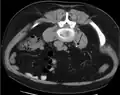

Imaging studies

Calcium-containing stones are relatively radiodense (opaque to X-rays), and they can often be detected by a traditional radiography of the abdomen that includes the kidneys, ureters, and bladder (KUB film).[59] KUB radiography, although useful in monitoring size of stone or passage of stone in stone formers, might not be useful in the acute setting due to low sensitivity.[60] Some 60% of all renal stones are radiopaque.[61][62] In general, calcium phosphate stones have the greatest density, followed by calcium oxalate and magnesium ammonium phosphate stones. Cystine calculi are only faintly radiodense, while uric acid stones are usually entirely radiolucent.[63]

Otherwise a noncontrast helical CT scan with 5 millimeters (0.2 in) sections is the diagnostic method to use to detect kidney stones and confirm the diagnosis of kidney stone disease.[16][57][61][66][7] Near all stones are detectable on CT scans with the exception of those composed of certain drug residues in the urine,[59] such as from indinavir.

Where a CT scan is unavailable, an intravenous pyelogram may be performed to help confirm the diagnosis of urolithiasis. This involves intravenous injection of a contrast agent followed by a KUB film. Uroliths present in the kidneys, ureters, or bladder may be better defined by the use of this contrast agent. Stones can also be detected by a retrograde pyelogram, where a similar contrast agent is injected directly into the distal ostium of the ureter (where the ureter terminates as it enters the bladder).[61]

Renal ultrasonography can sometimes be useful, because it gives details about the presence of hydronephrosis, suggesting that the stone is blocking the outflow of urine.[59] Radiolucent stones, which do not appear on KUB, may show up on ultrasound imaging studies. Other advantages of renal ultrasonography include its low cost and absence of radiation exposure. Ultrasound imaging is useful for detecting stones in situations where X-rays or CT scans are discouraged, such as in children or pregnant women.[67] Despite these advantages, renal ultrasonography in 2009 was not considered a substitute for noncontrast helical CT scan in the initial diagnostic evaluation of urolithiasis.[66] The main reason for this is that, compared with CT, renal ultrasonography more often fails to detect small stones (especially ureteral stones) and other serious disorders that could be causing the symptoms.[14]

On the contrary, a 2014 study suggested that ultrasonography should be used as the initial diagnostic imaging test, with further imaging studies be performed at the discretion of the physician on the basis of clinical judgment, and using ultrasonography rather than CT as an initial diagnostic test results in less radiation exposure and equally good outcome.[68]